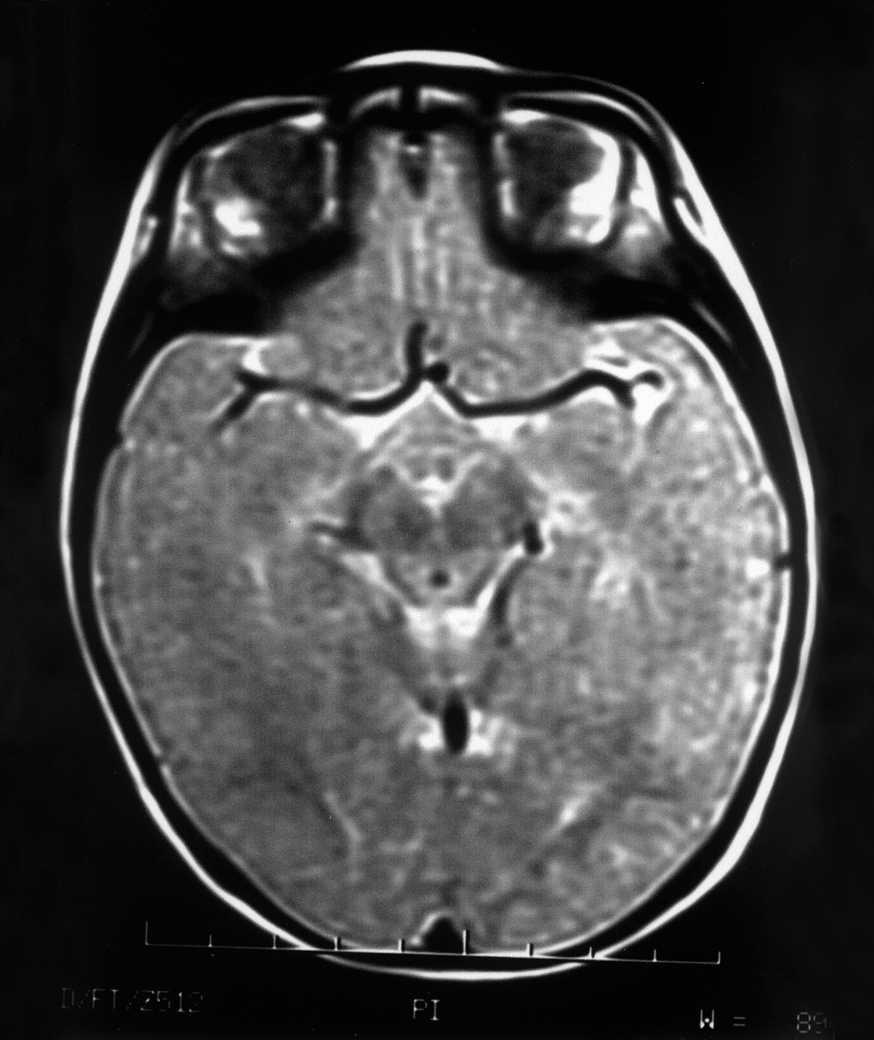

Las exploraciones complementarias realizadas fueron normales: hemograma, bioquímica sérica elemental, creatinfosfocinasa, ácido láctico, piruvato, aminoácidos en suero, ácidos orgánicos en orina, ácidos grasos libres en plasma, carnitina sérica total, carnitina libre, acilcarnitina, cociente acil/libre, equilibrio acidobásico, amonio, hormonas tiroideas, cariotipo, citoquímica de líquido cefalorraquídeo, electromiograma y velocidad de conducción motora de nervio peroneo, biopsia de músculo con estudio estructural, histoquímico y de cuantificación de enzimas de la cadena respiratoria mitocondrial, estudio del ADN mitocondrial de músculo en búsqueda de las mutaciones T8993G, T8993C y A9176C, deleciones únicas o múltiples y depleción por Southern blot, test de edrofonio, estudio de potenciales evocados auditivos del tronco cerebral y una tomografía computarizada (TC) craneal (fig. 1). Se realizaron tres estudios de resonancia magnética (RM) craneal a los 7, 9 y 15 meses de vida que mostraron alteración en la intensidad de la señal en tegmento mesencefálico, pontino y bulbar, más marcado en regiones dorsales (figs. 2 y 3).

Figura 2.RM craneal: secuencia ponderada en T2 a nivel del polígono. Hiperintensidad de la señal del tegmento paramediano y sustancia gris periacueductal.